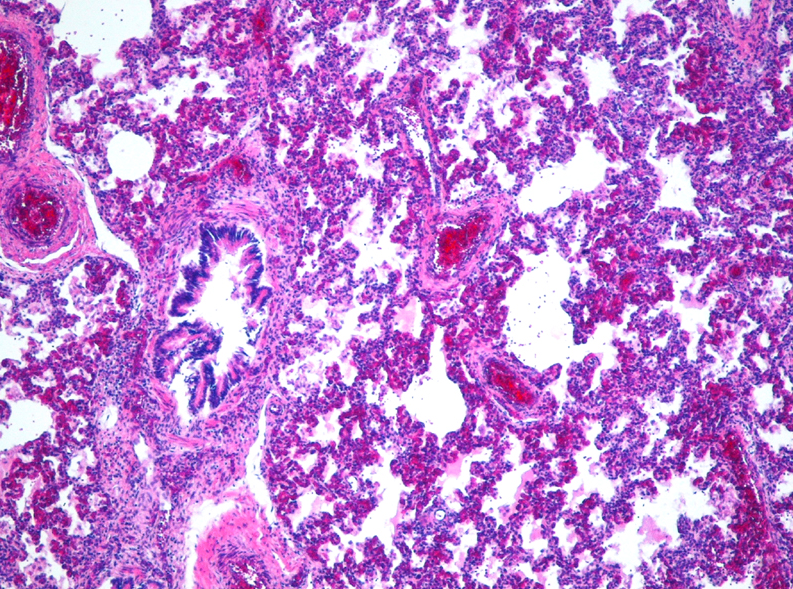

Identify:

Interstitial pneumonia

This lesion can be complicated by?

-Can be complicated by HYALINE MEMBRANES